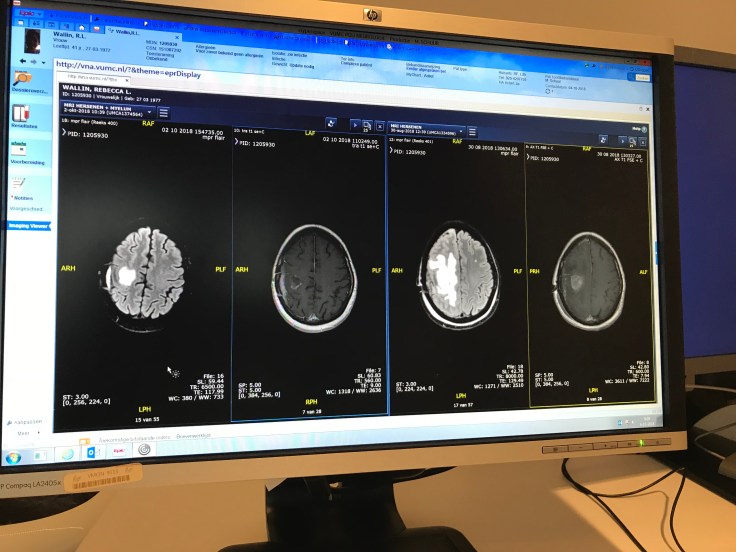

Quick recap; the first priority was to tackle Dastardly, the first of my two lesions; the one in my brain which was growing aggressively and paralysing the left side of my body. The treatment for this was Neuro surgery, followed by targeted high-dose Neuro radiation.

So on Tuesday, I had my review with my Neuro Radiologist, Dr Bartels, and he was happy with the results of the radiation. They’ll never 100% say it’s gone; but based on the last MRI, he’s confident that the cells he sees are just residue of the treatment – a bit like dried blood around an old wound. So he signed me off, saying: let’s catch-up in three months’ time. GET IN!